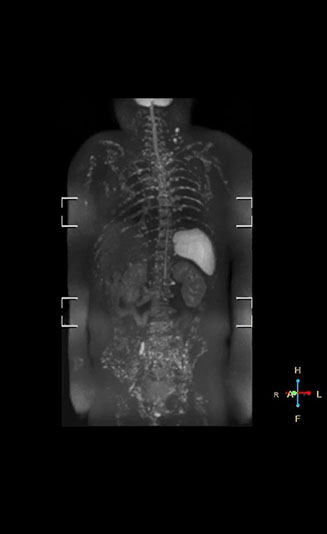

Coronal DWIBS is faster and improves image quality

“Switching to coronal DWIBS – rather than axial – further shortens scan time,” says Mr. Naka. “Important is that a dS SENSE factor of 5 shortens exam time while high image quality can be maintained, thanks to Ingenia’s dStream architecture.” He adds that the coronal orientation also avoids artifacts that are specific to combining axial images.

“When we use a coronal DWIBS acquisition, we can perform a full whole body examination, including other required sequences, within 30 minutes,” he says.

“This is considerably faster than the previously used exam with axial whole body DWI, which took more than 45 minutes,” he notes. “A shorter exam is more patient-friendly and allows us to also use it on patients in poor health who would have difficulty tolerating a long exam. Limiting the exam time is also helpful for scheduling, because it fits in a normal single exam timeslot.”